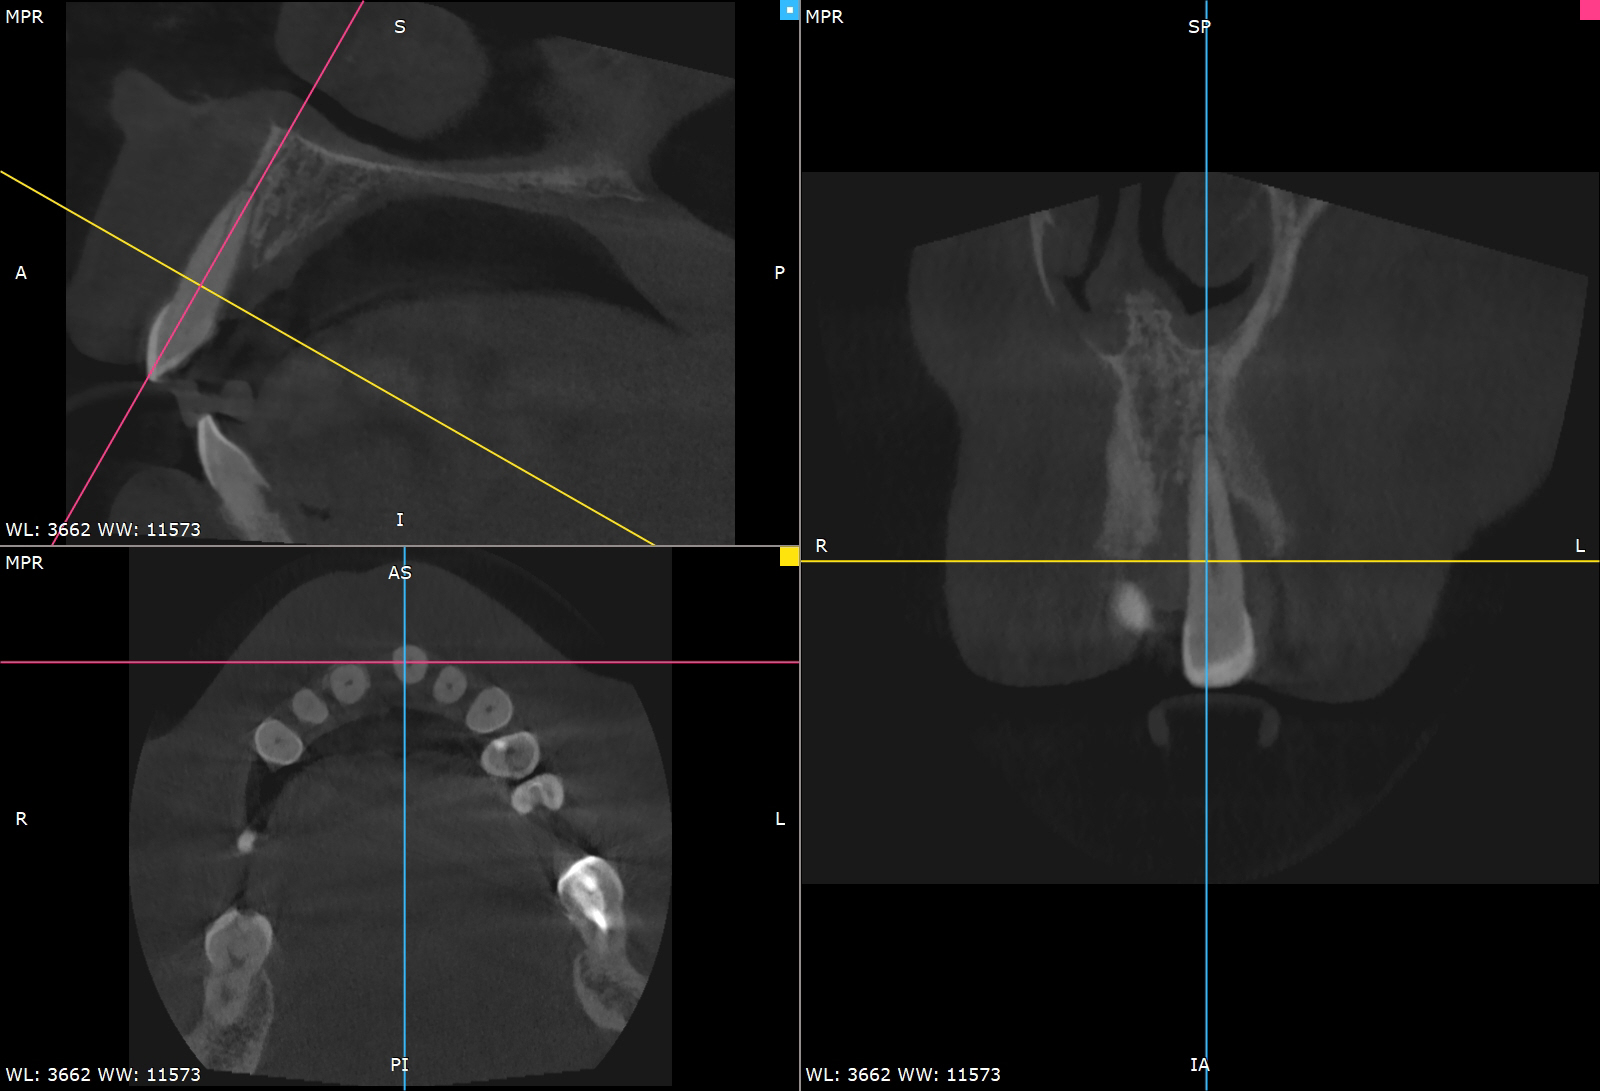

Pre-operative planning was performed using the DICOMLAB digital planning platform. The workflow included a pre-operative CBCT scan of the upper jaw and a digitalintraoral scan.

These datasets were merged within the DICOMLAB software to allow prosthetically driven implant planning.

Planned implant:

DSI Conical Implant - 4.3 mm diameter, 13 mm length.

A custom surgical guide was fabricated using the DICOMLAB open platform, which allows surgical guide production for most implant systems.